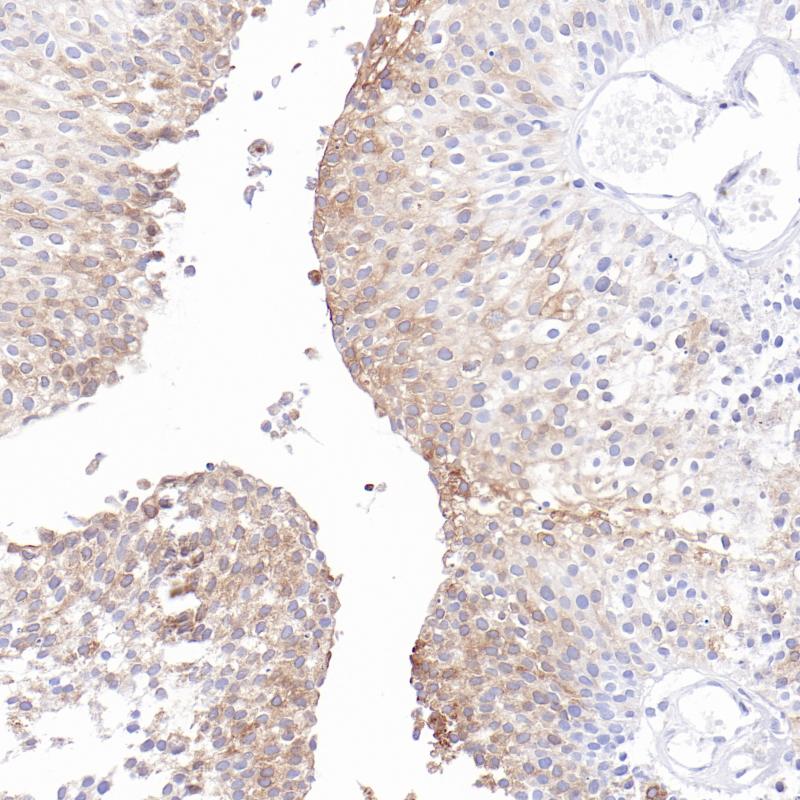

肝MHC II(BP6270)染色

MHC Ⅱ

重组兔单克隆抗体

主要组织相容性复合体 II 类(MHC II 类)分子是在巨噬细胞、树突细胞和 B 细胞等抗原呈递细胞表面表达的异二聚体的跨膜糖蛋白。在人体中,MHC II 类蛋白复合体被人白细胞抗原基因复合体 (HLA) 编码。MHC II可在 B 淋巴细胞、活化的 T 淋巴细胞、活化的自然杀伤 (NK) 细胞及各种肿瘤组织中均有表达。

阳性对照

肝

亚细胞定位

细胞膜